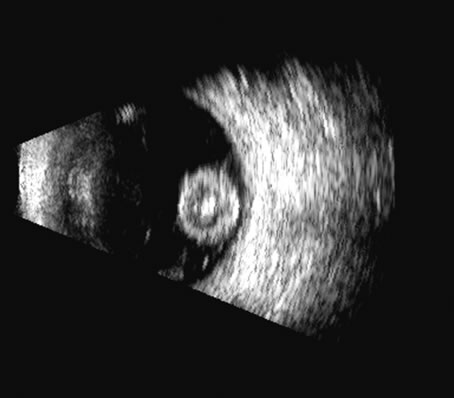

The choroid, like the retina, is highly reflective and may resemble the retina when detached. Its thickness, which includes the retina, Bruch's membrane, and the choriocapillaris (tunica ruyschiana) is not usually differentiable when measured with routine ultrasound;12 however, it may be measured with digital techniques.18 Anatomically, the choroidal elevation is usually a smoothly round, convex surface, limited posteriorly by the vortex veins and anteriorly at any point up to the base of the iris (Fig. 17). The choroidal space should be examined for echoes (blood) or a clear zone, as seen with effusion or the serous part of a hemorrhage. In evaluating membranes from retina or choroid, it is always helpful to repeat the examinations at a later time.

Fig. 14. A B-scan of an eye with “kissing” choroidal detachments. The smooth convex outline from the ciliary body back to the near periphery of the posterior pole can be seen. The choroidal space, though filled with blood, may often appear anechoic due to the recent, “fresh” nature of the hemorrhage.